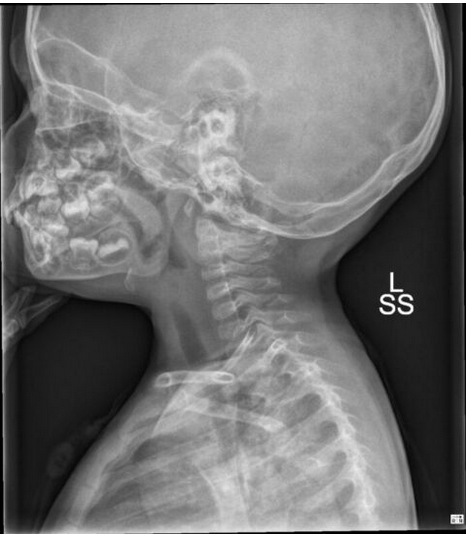

4yo male with no PMH, is in the ED with CC of "it sounds like he cant breath". Child is adopted, immunization hx is unknown. Mom says he has had trouble drinking for last few hours.

Patient is sitting on the stretcher drooling slightly, has moderate inspiratory stridor, is tachycardic, tachypneic, and has some retractions. Periodically he clears his throat and coughs. Nothing is visible in his mouth.

What urgently needs to happen?

Acute Epiglottitis

Intubation in the OR, ENT consult, PICU admission, antibiotics